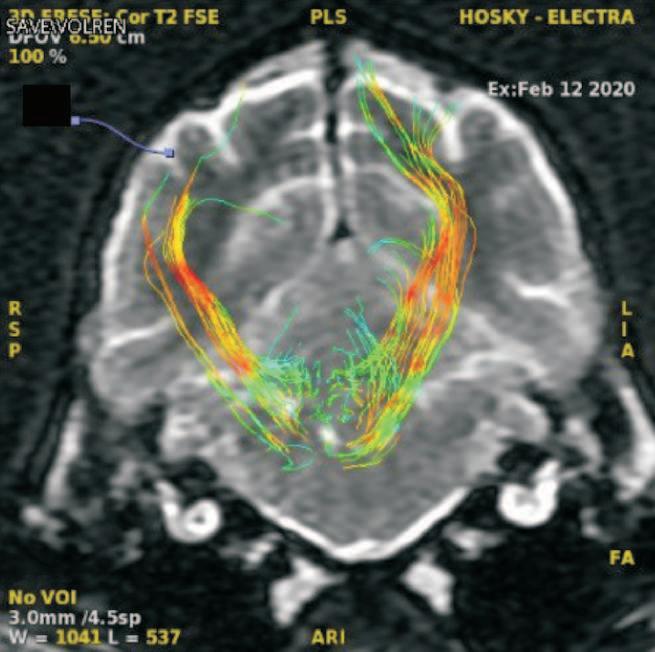

Tracto corticoespinal en vista coronal. (p. ??).

Uso del tensor de difusión como una herramienta de diagnóstico en las enfermedades del sistema nervioso central en perros. Reporte de un caso en un husky siberiano con alteraciones del comportamiento.

José Alberto Toscano-Zapién, Patricia Rizo-Espinoza, Ismael Hernández-Avalos, Liliana Blancas-Espinoza, Erick Humberto Pasaye-Alcaraz, Edna Elisa García-Vences, Raúl Silva-García

Use of the diffusion tensor as a diagnostic tool in diseases of the central nervous system in dogs. Report of a case in a Siberian husky with behavioral alterations. .